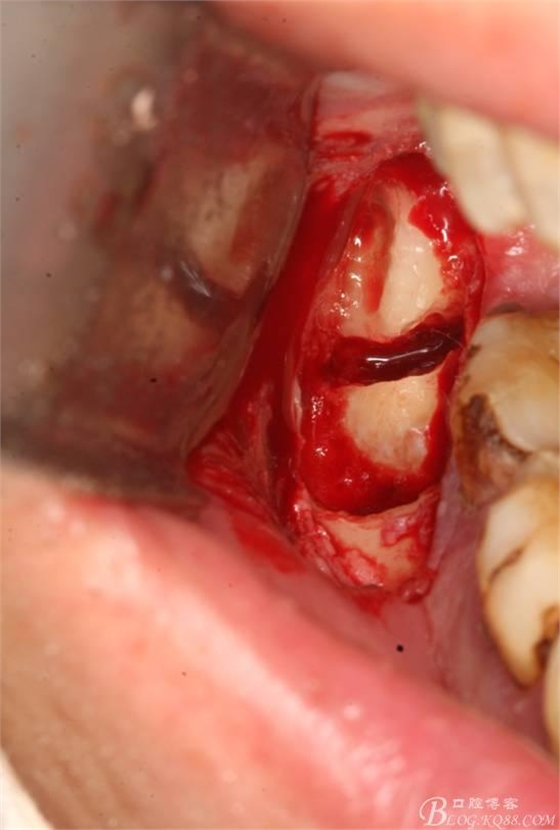

6.橫斷牙冠

7.取出牙冠

8.清理拔牙創(chuàng)